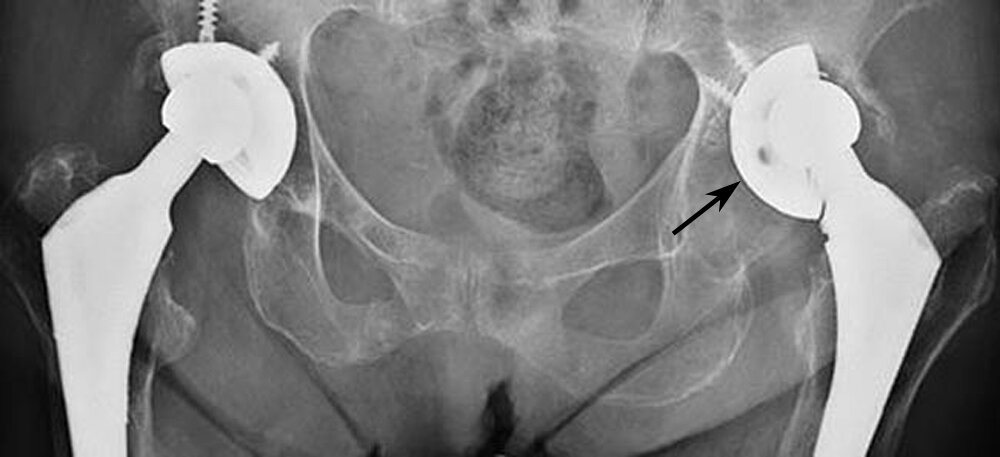

Dr. Scott Tulloch will use a range of diagnostic methods to determine why your hip replacement is failing. These include:

• X-rays: Used to identify loosening, fractures, malalignment, or component wear.

• MRI or CT scan: Provides detailed images of soft tissue, bones, and the position of the implant components.

• Revision Hip Replacement: If the implant is loose, misaligned, worn out, or fractured, a revision hip replacement may be required. This involves removing the old components and replacing them with new ones.